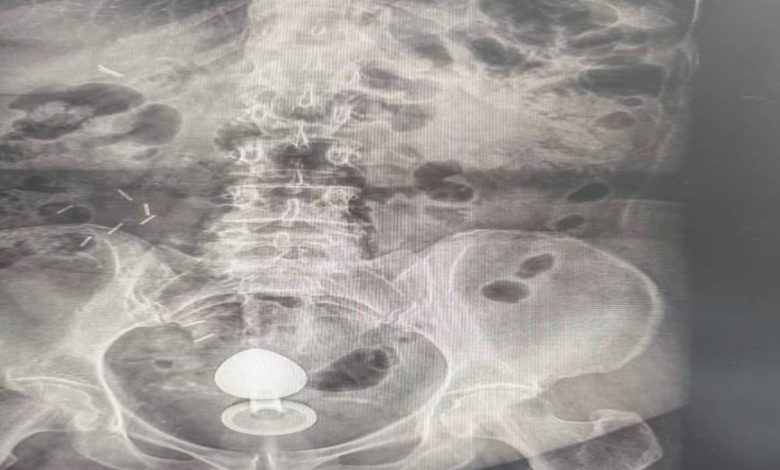

O caso foi atendido pelo cirurgião coloproctologista Daniel Brosco. Segundo o médico, a paciente contou que, na verdade, estava usando o sex toy para ajudar com a constipação intestinal, e não com finalidade sexual. O médico alerta que isso é contraindicado.

O médico explica que a paciente tinha um quadro de pólipos no intestino — quando a mucosa apresenta um crescimento anormal que pode evoluir para câncer. Com isso, a parede intestinal era mais sensível, aumentando o risco de perfuração.

Brosco afirma que ela passou pelo procedimento para retirada do objeto e passa bem, mas que o caso é um alerta sobre o uso desse tipo de brinquedo. O uso inadequado pode levar a complicações como lacerações, sangramentos e perfurações intestinais — especialmente em pacientes com condições prévias que tornam a mucosa mais sensível.